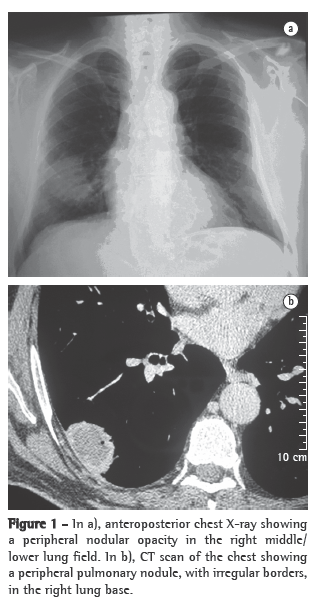

With treatment, the patient presented improvement of the clinical manifestations and the pulmonary alterations resolved (Figure 3).

Imaging studies showed an extensive unilateral nodular lesion. This finding is uncommon in WG and, therefore, there was diagnostic difficulty in view of the possibility of a malignant disease. What is expected in this type of vasculitis is pulmonary infiltration or bilateral multiple nodules, which can be accompanied by cavitations (in 50% of the cases).(8) The next step was then to resort to tomography-guided percutaneous biopsy, a procedure that has high sensitivity, specificity and accuracy, the last ranging from 84.5% to 90%, depending directly on the size of the lesion. The principal reason for requesting the procedure is to determine malignancy in solid pulmonary lesions.(9,10)